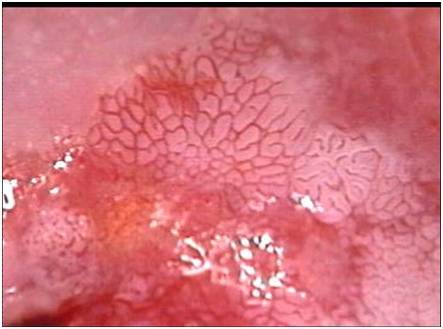

做阴道镜的体位是膀胱截石位具体解释如下体位定义膀胱截石位是一种常用的妇科检查体位,患者仰卧于检查床上,两腿屈曲分开置于支腿架上,臀部抬高,这种体位便于医生窥开阴道并显露宫颈体位作用在做阴道镜检查时,医生需要用阴道镜的光束照射在宫颈上,并观察宫颈表面的血管上皮在涂醋酸溶液后的。